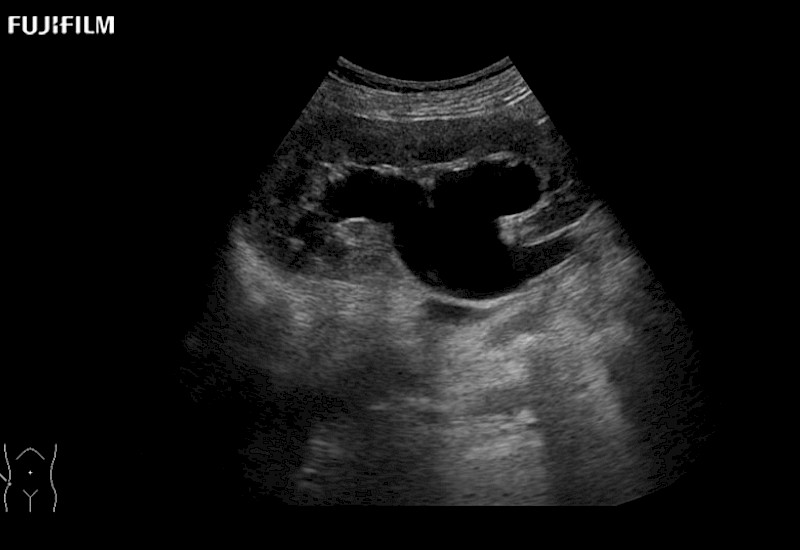

The ARIETTA 750 incorporates all of the proven technologies and functions that medical professionals have come to expect from Fujifilm Healthcare.

ARIETTA 750 is the definitive diagnostic ultrasound solution for any clinical setting - Private Office, Imaging Center, or Hospital. The ARIETTA platform provides the ultimate in clinical performance with its state-of-the-art features and large user-friendly display.

The ARIETTA 650 DI combines trusted Fujifilm Healthcare technologies and features tailored for surgical oncology.

Designed to meet the demands of surgeons, the ARIETTA 650 DI offers precise guidance. Its advanced capabilities and large, intuitive display offer accurate and efficient care in operating rooms and specialized surgical settings.